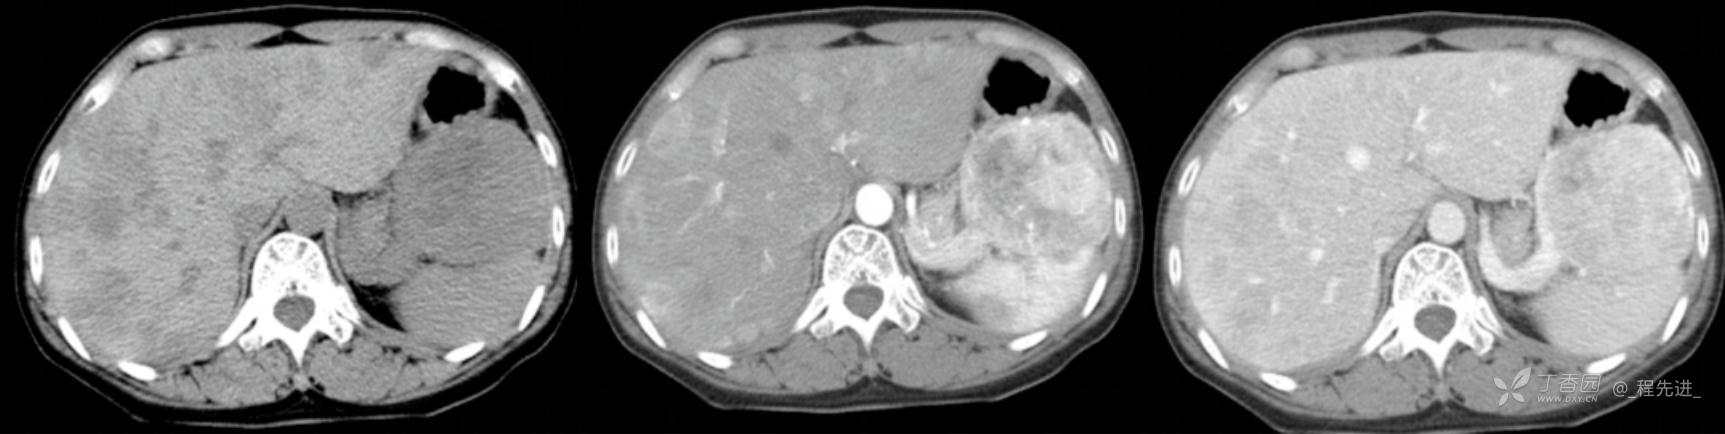

图像左边为平扫,中间的是动脉期,右边的是静脉期